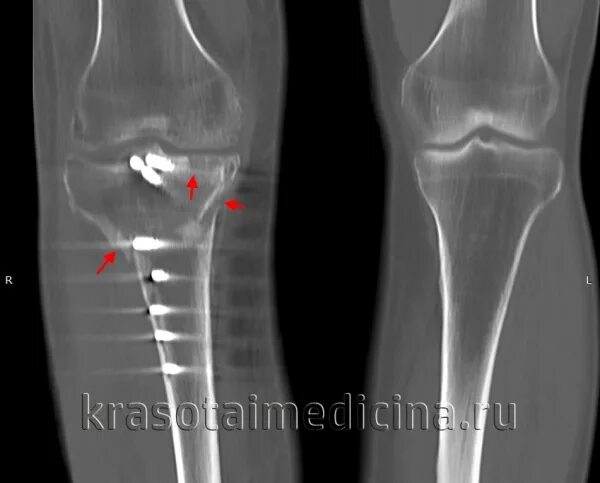

Перелом без причины